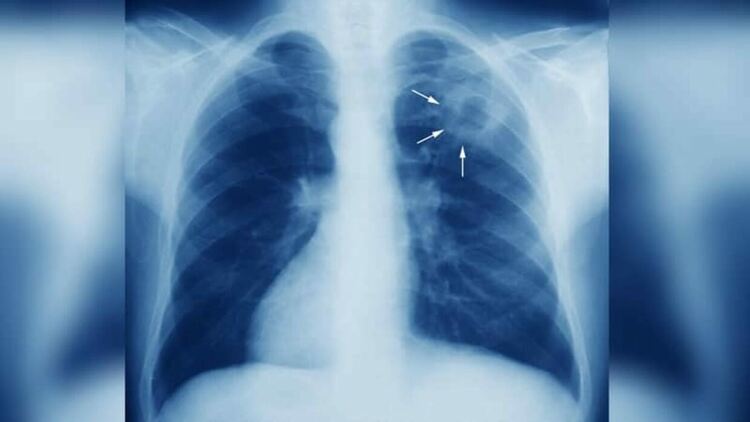

Туберкулозата (на латински: Tuberculosis), разговорно наричана също охтика или особено в литературата „Жълтата гостенка“, е хронично протичащо специфично възпалително заболяване, което засяга предимно белите дробове, но може да засегне и централната нервна система, лимфните съдове, храносмилателната система, костите, ставите или кожата.